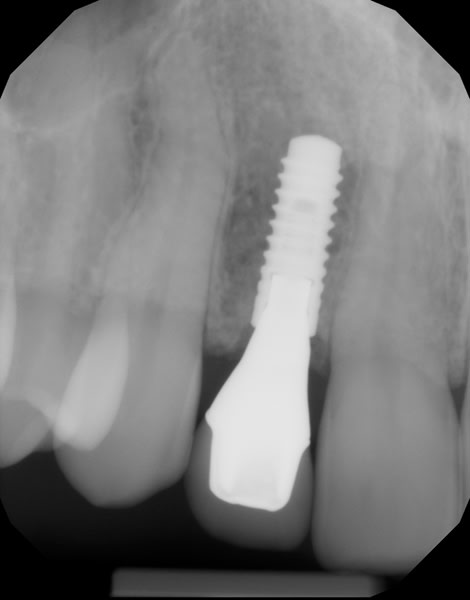

Both provisional restorations were removed, the definitive abutments were connected, and the abutment screws were torqued to 35 Ncm. The accuracy of the abutment margins at the gingival level, as transferred from the original custom scan body, is demonstrated in Figure 24. A cotton pellet and elastic, single-component, light-cured resin was placed to close the abutment access hole and light cured. The definitive restorations were cemented with radiopaque glass ionomer luting cement (Figure 25 through Figure 29).